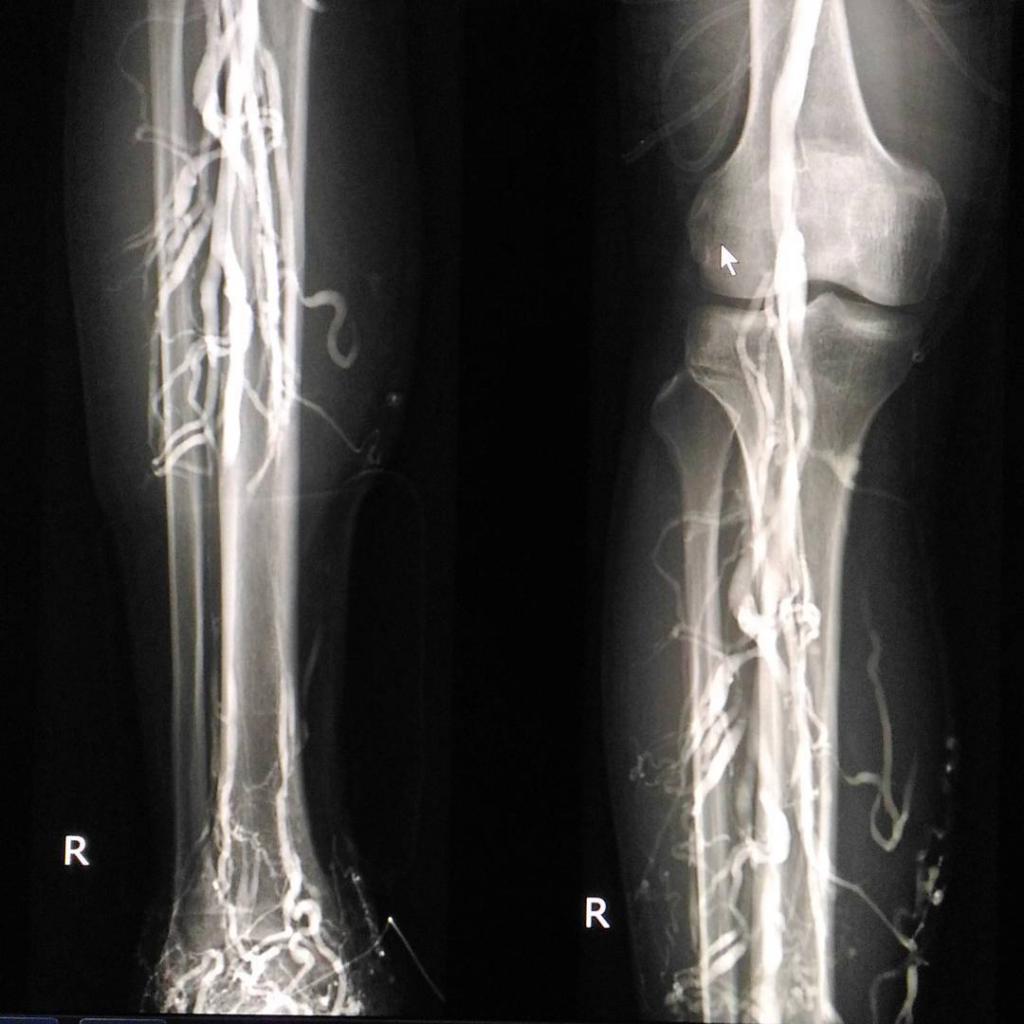

Проверка сосудов

Лечащий врач обязан тщательно оценить состояние сосудов на момент обращения пациента. Важно обратить внимание на степень расширения вен, их извитость, наличие дистрофических изменений и тромбы. Тромбы могут формироваться не только из-за повышенной вязкости крови. При атеросклерозе в сосудах также возникают бляшки, которые препятствуют нормальному кровообращению. Чтобы исключить наличие атеросклеротических бляшек, специалист может назначить дополнительный анализ крови на уровень холестерина.

Обследование проводит флеболог с использованием специализированного оборудования. Особое внимание уделяется состоянию крупных сосудов нижних конечностей и внутренних вен, таких как вены пищевода. Основные методы диагностики включают ультразвуковое исследование вен и флебографию, которая представляет собой рентгенологическое исследование с использованием контрастного вещества.